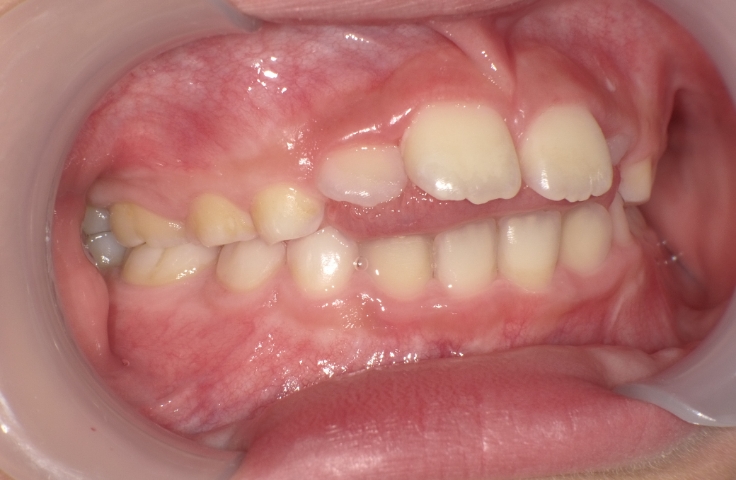

当医院では、歯並びに対する各種治療を行っております。

セファロ写真(横顔のレントゲン)や歯型を分析し、それぞれにあった治療プランをご提案致します。

また、ワイヤー矯正やインビザライン矯正(マウスピース矯正)等、症例に合わせて行っております。

お子様においては、プレオルソ治療も行っております。受け口や出っ歯等、早期に解決すべき歯並びに対して、高いコストパフォーマンスを上げております。